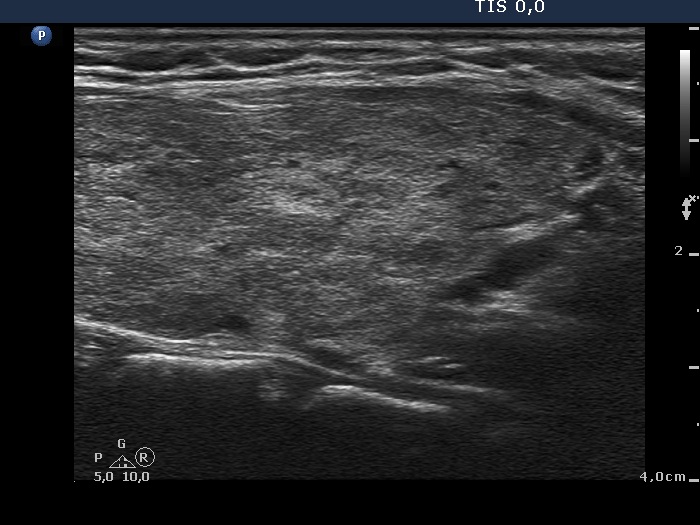

Case 419 (ultrasonographic picture 7)

Lower part of the left lobe, longitudinal view.